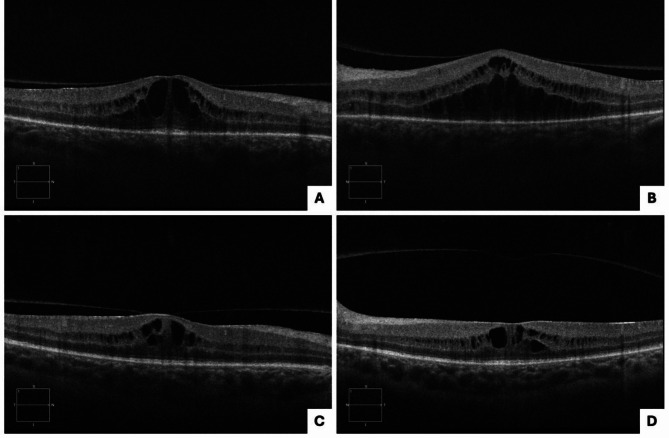

Case series: Recommended initial treatment for all patients was 14 days of intravenous penicillin. Oral prednisone was added 48 h after initiation of penicillin therapy. Case 1: A 48-year-old female presented with gradual vision loss for two months. Fundus imaging revealed syphilitic outer retinopathy (SOR), papillitis, and acute syphilitic posterior placoid chorioretinopathy (ASPPC). After treatment, she had persistent cystoid macular edema (CME) and was treated with intravitreal triamcinolone injections and ketorolac drops.

Case 2: A 24-year-old male presented with sudden vision loss for two days. On imaging, he had ASPPC, papillitis, and SOR. IV penicillin treatment was given for 10 days only. He had persistent SOR and was retreated with doxycycline and prednisone. Case 3: A 52-year-old male presented with eye pain and visual loss for one week. There was evidence of ASPPC and papillitis on imaging. One month after treatment, he had persistent papillitis and was restarted on oral prednisone. One year later, he was found to have recurrent ASPPC and was confirmed to be reinfected with syphilis, for which he was retreated.